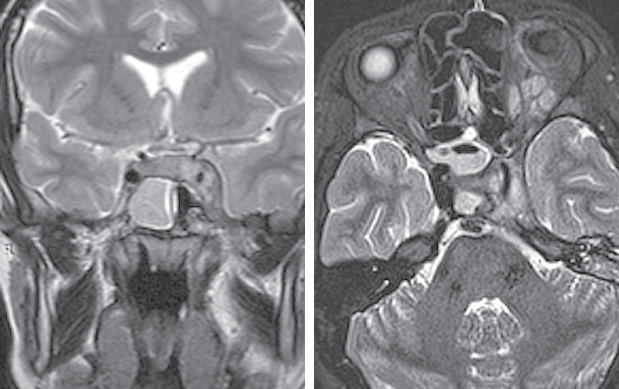

Рис. 5. Магниторезонансная томография головы от 10.11.2021: правосторонний сфеноидит, тромбоз кавернозного синуса слева. Слева — коронарная проекция в режиме Т2. Тотальное затенение правой половины пазухи клиновидной кости, сужение кавернозного синуса слева; справа — аксиальная проекция в режиме Т2. Признаки тромбоза кавернозного синуса слева

Fig. 5. Magnetic resonance imaging of the head from 10.11.2021: right-sided sphenoiditis, thrombosis of the cavernous sinus on the left. Left: coronal projection in T2 mode. Total shading of the right half of the sphenoid sinus, narrowing of the cavernous sinus on the left; right: axial projection in T2 mode. Signs of thrombosis of the cavernous sinus on the left

Рис. 6. Магнитно-резонансная томограмма головного мозга. Признаки тромбоза кавернозного синуса. 1 — Венозный застой в ретробульбарной клетчатке; 2 — cужение просвета сифона внутренней сонной артерии слева; 3 — неоднородность структуры

Fig. 6. Signs of cavernous sinus thrombosis on magnetic resonance imaging of the brain. 1 — Venous congestion in the retrobulbar tissue; 2 — narrowing of the lumen of the siphon of the internal carotid artery on the left; 3 — structure heterogeneity